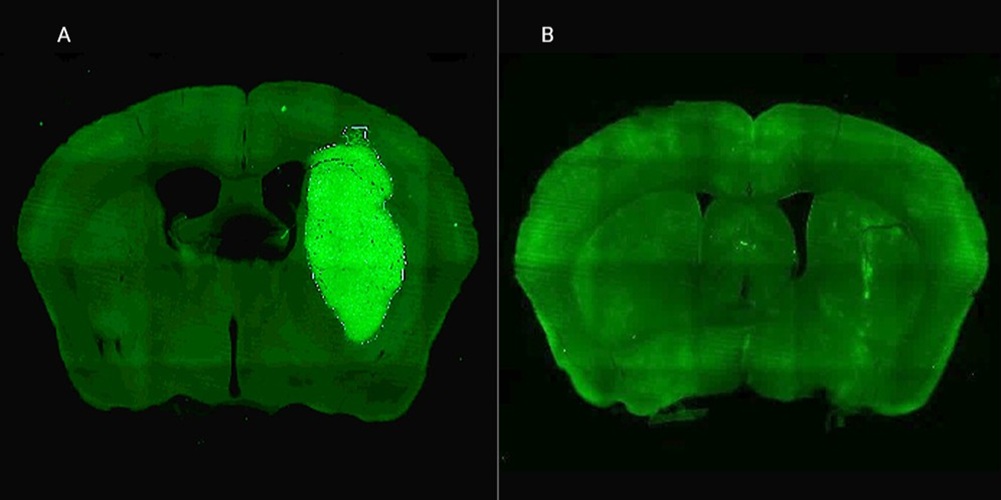

B) El tumor desaparece gracias a la administración de la estrategia terapéutica diseñada por los especialistas del CONICET.

El siguiente paso fue probar la estrategia en un modelo vivo. Para llevar el inhibidor P60 de forma sostenida y directa al tumor cerebral en ratones, el equipo desarrolló un ingenioso sistema de «delivery»: un virus modificado (un vector adenoviral) que, al ser inyectado en la zona, funciona como una bio-fábrica que produce el péptido P60 dentro de las células tumorales.

El resultado de la terapia combinada fue contundente y esperanzador. «Una inyección intratumoral del vector inhibió el crecimiento del tumor y mejoró notablemente la respuesta a la quimioterapia, llevando a la erradicación del tumor y sobrevida a largo plazo en un tercio de los ratones», revela Candolfi. Además, un dato clave es que no observaron efectos neurotóxicos, lo que sugiere un buen perfil de seguridad.